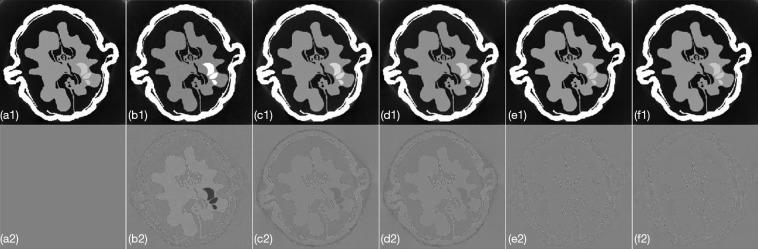

To improve image reconstruction quality for photon-counting CT, we propose an algorithm based on the subspace-assisted multi-prior information, including global, nonlocal, and local priors, for spectral CT reconstruction. Specifically, the algorithm first maps spectral CT images, which exhibit global low-rank characteristics, to low-dimensional eigenimages using subspace decomposition. Then, similar image patches are extracted based on the manifold structure distance from highly correlated eigenimages in both spectral and spatial domains. These patches are stacked to form a nonlocal full-channel tensor group. Subsequently, non-convex structural sparsity is applied to this tensor group through adaptive dictionary learning, exploiting nonlocal similarity. Finally, the alternating direction method of multipliers (ADMM) is applied to solve the optimization model iteratively.

The simulated walnut and real mouse data were applied to validate the effectiveness of the proposed method. In the simulation experiments, the proposed method reduced the root mean square error (RMSE) by 87.74%, 86.88%, 67.01%, 46.42%, and 13.51% compared to the respective state-of-the-art five comparison methods. The time taken for one iteration of the proposed algorithm was as low as 32.57 seconds, which was 92.07% less than framelet tensor nuclear norm [framelet tensor sparsity with block-matching method (FTNN)] method and 74.13% less than total variation regularization [tensor nonlocal similarity and local TV sparsity method (ITS_TV)] method, the other two tensor block-matching (BM)-based comparison methods. The material decomposition results in real mouse data further validated the accuracy of the proposed method for different materials.